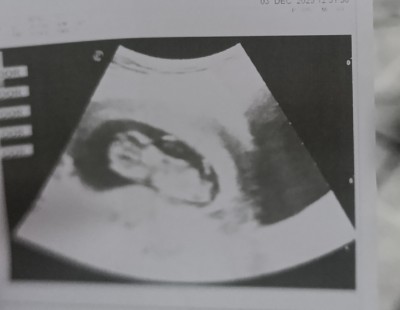

11+5 sizce cinsiyet tahmini nedir

Gebelik haftası 11+5

Burda 11+ 5 haftalık doktor tahmin için erken dedi

Kız gibi çıkıntı göremedim sağlıkla gelsin

Erkek. Cnm. Bence kese. Karın yapısı. Felan